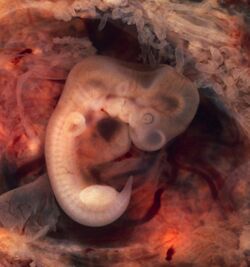

While a fetus of ectopic pregnancy is typically not viable, very rarely, a live baby has been delivered from an abdominal pregnancy. In such a situation the placenta sits on the intra-abdominal organs or the peritoneum and has found sufficient blood supply. This is generally bowel or mesentery, but other sites, such as the renal (kidney), liver or hepatic (liver) artery or even aorta have been described. Support to near viability has occasionally been described, but even in Third World countries, the diagnosis is most commonly made at 16 to 20 weeks' gestation. Such a fetus would have to be delivered by laparotomy. Maternal morbidity and mortality from extrauterine pregnancy are high as attempts to remove the placenta from the organs to which it is attached usually lead to uncontrollable bleeding from the attachment site. If the organ to which the placenta is attached is removable, such as a section of bowel, then the placenta should be removed together with that organ. This is such a rare occurrence that true data is unavailable and reliance must be made on anecdotal reports.[37][38][39] However, the vast majority of abdominal pregnancies require intervention well before fetal viability because of the risk of bleeding.